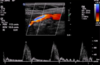

Carotid DUS imaging shown below. Diagnosis?

near-total ICA occlusion

note significant ICA plaque with low velocities distal to lesion (“falling off spencer-reid curve”)